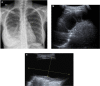

We present a case of a 14-year-old girl, Bacillus Calmette-Guérin (BCG) vaccinated, who presented with vague symptoms of abdominal pain, weight loss, and fatigue. Imaging studies revealed a pelvic mass, later found to be pelvic tuberculosis, a rare diagnosis to consider at this age. The diagnostic approach was difficult, since all investigations pointed strongly to a malignancy, from clinical, imaging (ultrasound and magnetic resonance), laboratory (elevated CA-125), and even macroscopic findings at laparotomy. Histopathology was the first hint (noncaseous granulomata), but the ultimate documentation of Mycobacterium tuberculosis relied on a persistent clinical suspicion, despite contradicting results. Surgical approach could have been mutilating, with irreversible consequences, considering it was a girl with a long reproductive life ahead. Tuberculosis is still a great masquerade, especially the extrapulmonary forms, and although infrequently seen at this age, it should thus be considered in the differential diagnosis of complex pelvic masses in order to avoid surgical iatrogeny/morbidity.